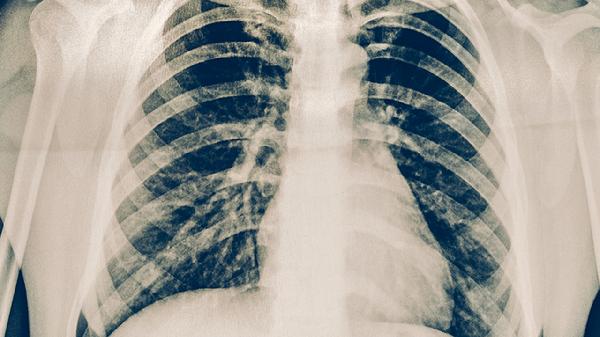

原發(fā)性肺結(jié)核的診斷主要依據(jù)胸部影像學(xué)檢查和結(jié)核菌素試驗(yàn)。胸部X線或CT可見(jiàn)肺內(nèi)原發(fā)病灶和肺門淋巴結(jié)腫大,形成啞鈴狀陰影。結(jié)核菌素試驗(yàn)陽(yáng)性有助于診斷,但需結(jié)合臨床表現(xiàn)和其他檢查結(jié)果綜合判斷。痰涂片找抗酸桿菌和痰培養(yǎng)檢查可幫助確診,分子生物學(xué)檢測(cè)如GeneXpert檢測(cè)可快速診斷結(jié)核分枝桿菌感染。